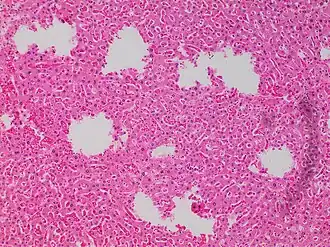

![Tearing artifacts, such as can be caused by: - Microtomy with a nick or blemish in the knife edge.[5] - Traction of the sections. - Too much or too little alcohol dehydration.[5] - Sectioning calcified parts, which can be decalcified or removed.[5]](./_assets_/Microscopy_of_liver_parenchyma_with_tearing_artifacts.jpg)

Staining artifacts by residual wax, resulting in pale areas where cellular structures are not discernible -